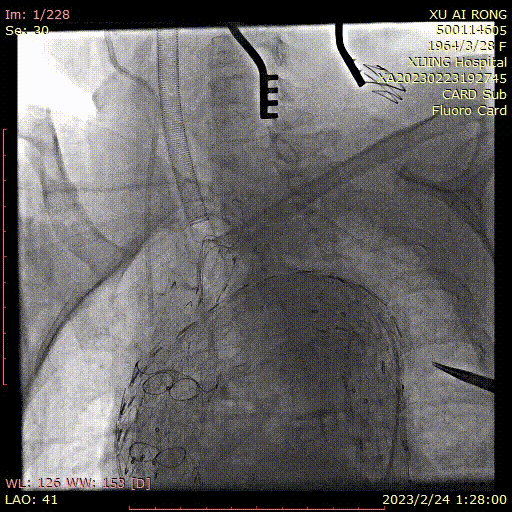

★ 病例4

王某,女,56岁,“突发胸背痛15小时”入院,主动脉CTA提示:升主动脉-腹主动脉管腔外可见新月形低密度影,主动脉弓前部可见溃疡,大小约0.6cm。

术前CTA

术前造影

术后造影

手术用时 95分钟